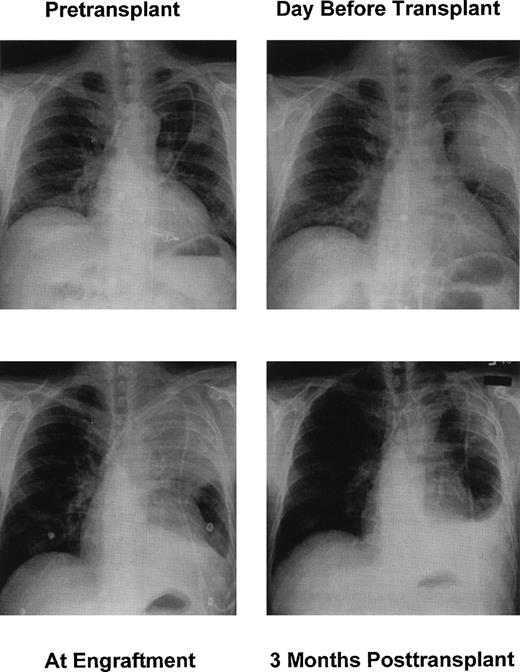

The pulmonary infiltrate on CXR progressed early after the transplant, and this was more likely caused by neutrophil infiltration after allogeneic engraftment. The infiltration then regressed over a 3-month period (Fig 2). The left pleural effusion persisted but was stable and sterile by culture. Specific therapy included 2.1 g of Ampho B (8/11/98 to 9/26/98), 7.8 g of ABCL (9/27/98 to 11/5/98), and 4.2 g of Voriconazole (266 mg intravenous twice a day from 11/6/98 to 1/6/99; 200 mg orally twice a day 1/7/99 to 1/30/99). Subsequently, the patient has been maintained to date on itraconazole, 300 mg twice a day orally. His renal insufficiency resolved after discontinuing Ampho B.

Chest x-rays. (Top left) Seven days before HSCT. (Top right) One day before HSCT. (Bottom left) Day 10 after HSCT. (Bottom right) Three months after HSCT.